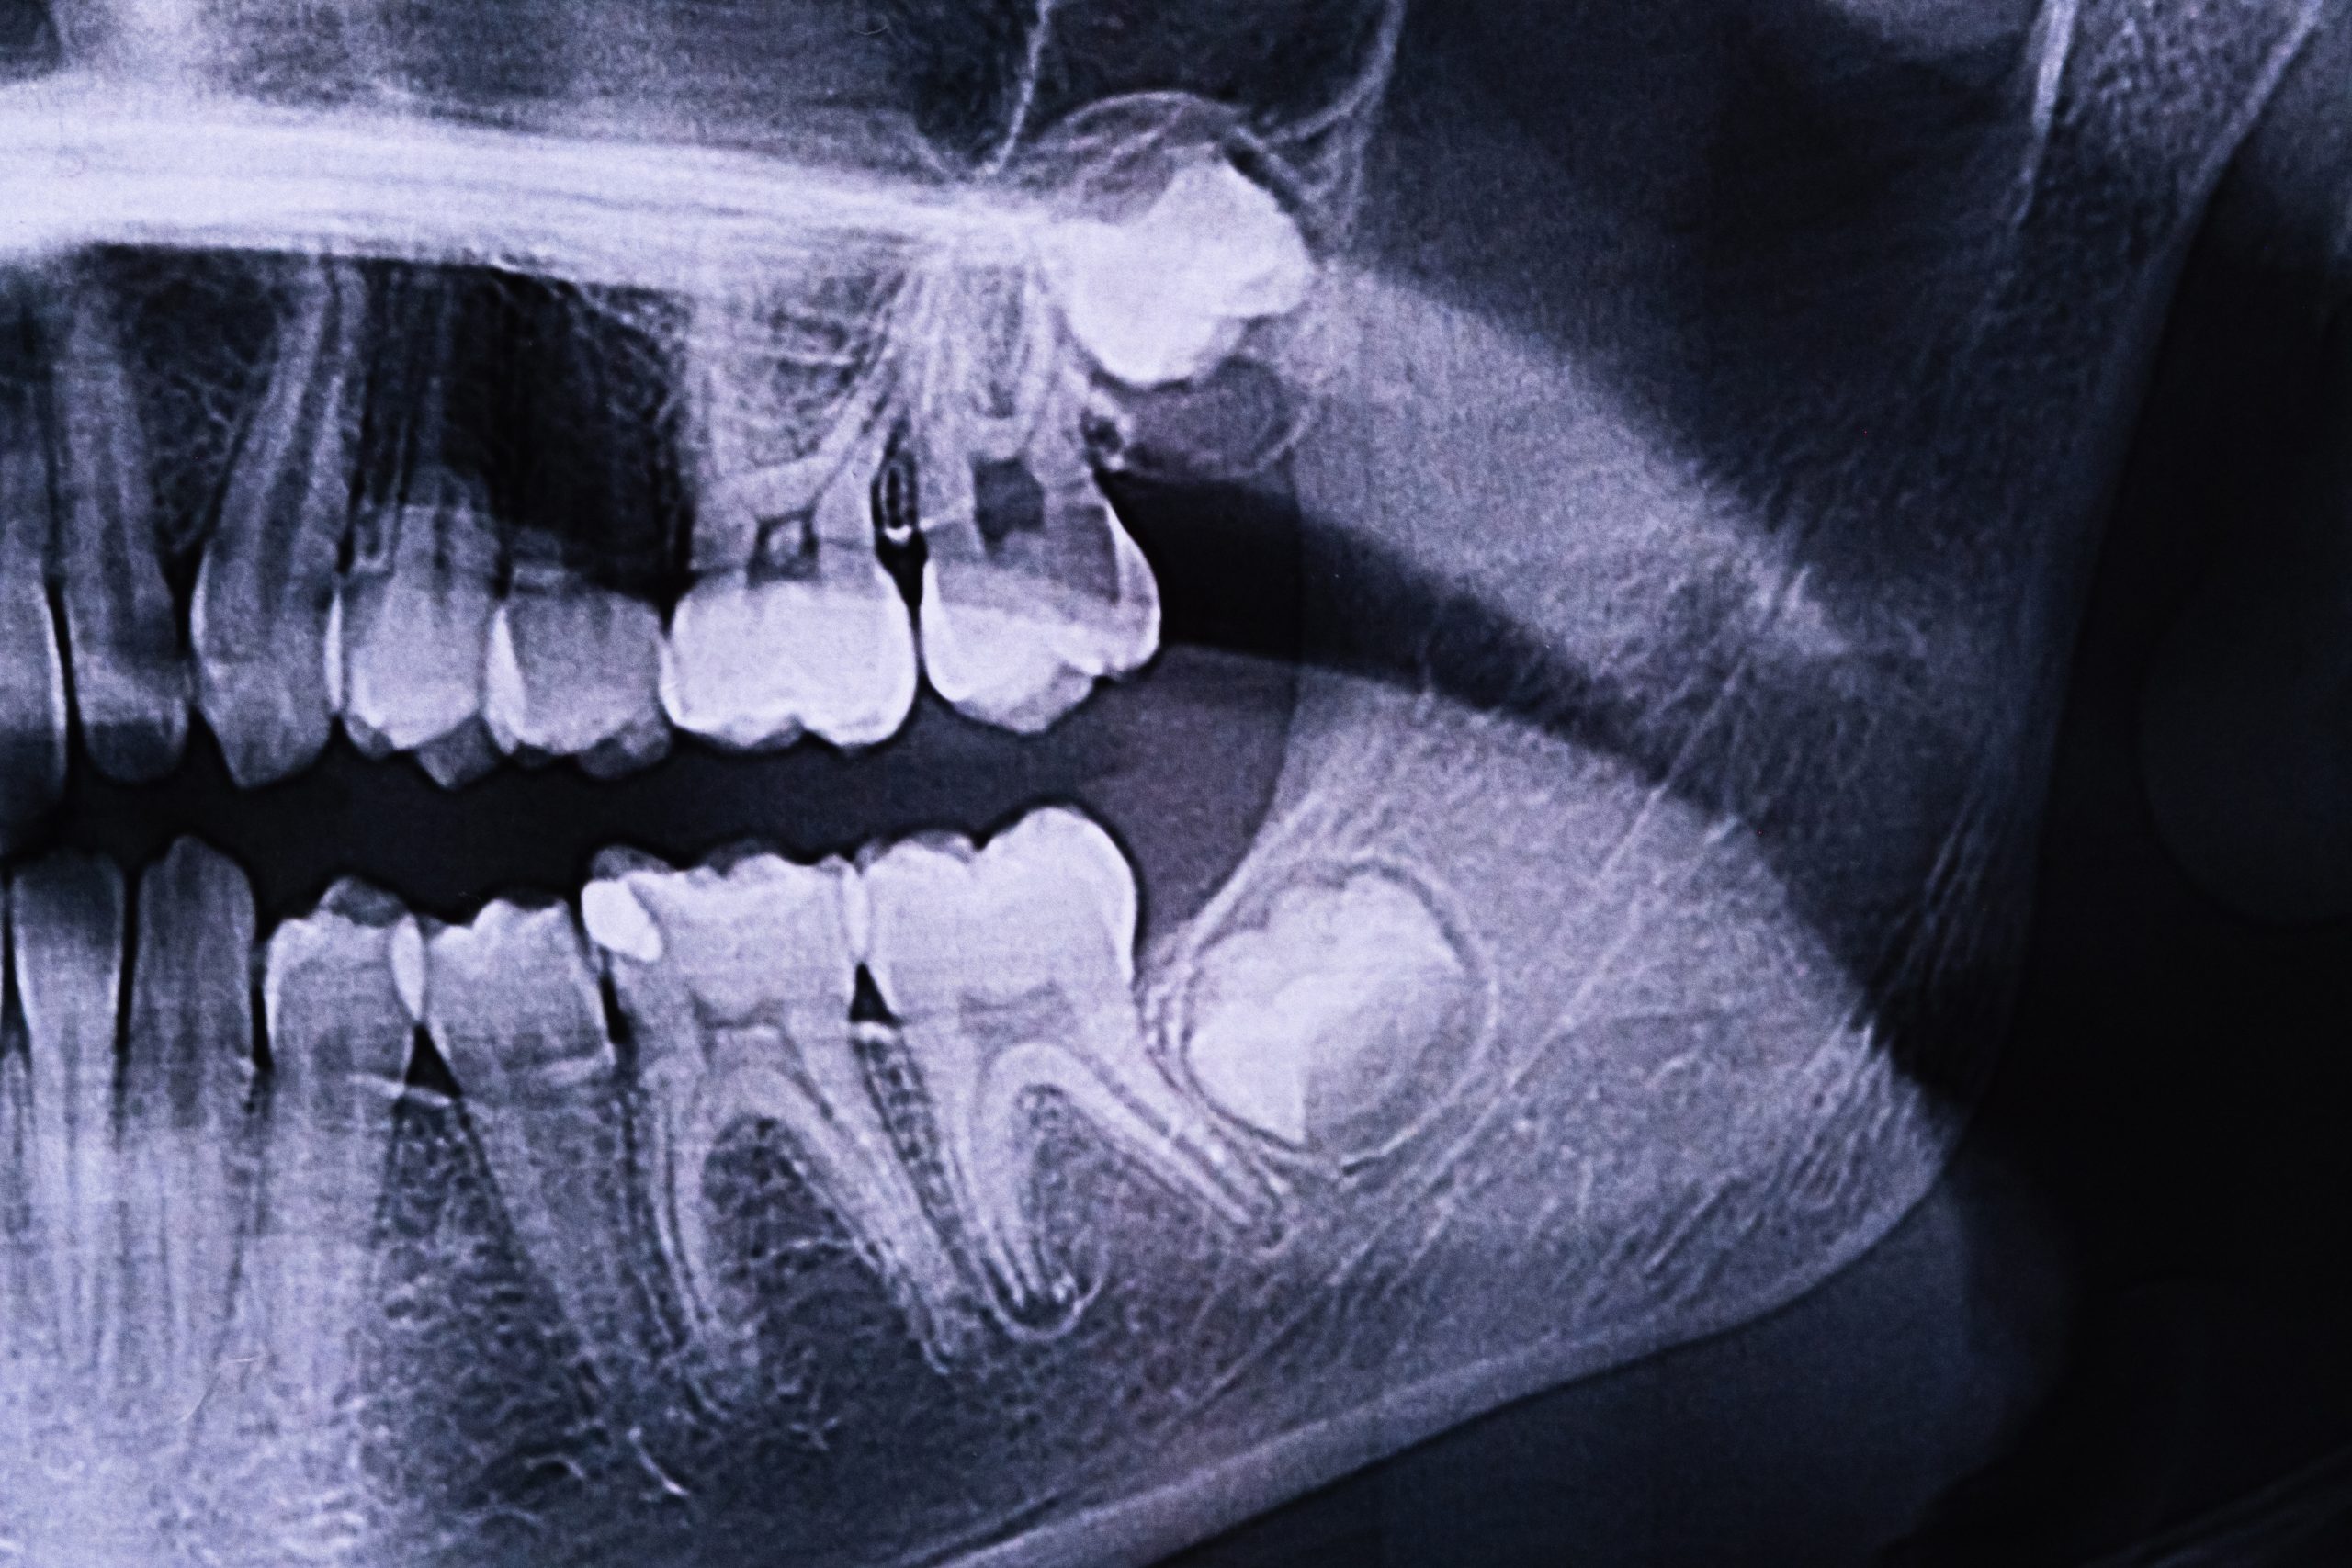

Las muelas del juicio son los terceros molares, que suelen erupcionar entre los 17 y los 25 años. En muchos casos, estas piezas no encuentran el espacio adecuado para salir correctamente, lo que da lugar a una erupción parcial o una inclusión dentaria (cuando quedan retenidas dentro del hueso o la encía). Esta situación puede derivar en infecciones, quistes, caries en los dientes adyacentes, o incluso en problemas ortodóncicos.

- Impactación dental, cuando la muela crece en ángulo o no erupciona por falta de espacio.

- Presencia de quistes o tumores odontogénicos asociados a muelas retenidas.

Cuando la intervención requiere una técnica quirúrgica más compleja, la cirugía maxilofacial es la especialidad indicada. El cirujano maxilofacial posee una formación médico-quirúrgica especializada que le permite abordar con precisión los casos de muelas retenidas, especialmente si están cercanas a estructuras nerviosas como el nervio dentario inferior.

- Evaluación preoperatoria con radiografía panorámica o escáner CBCT.